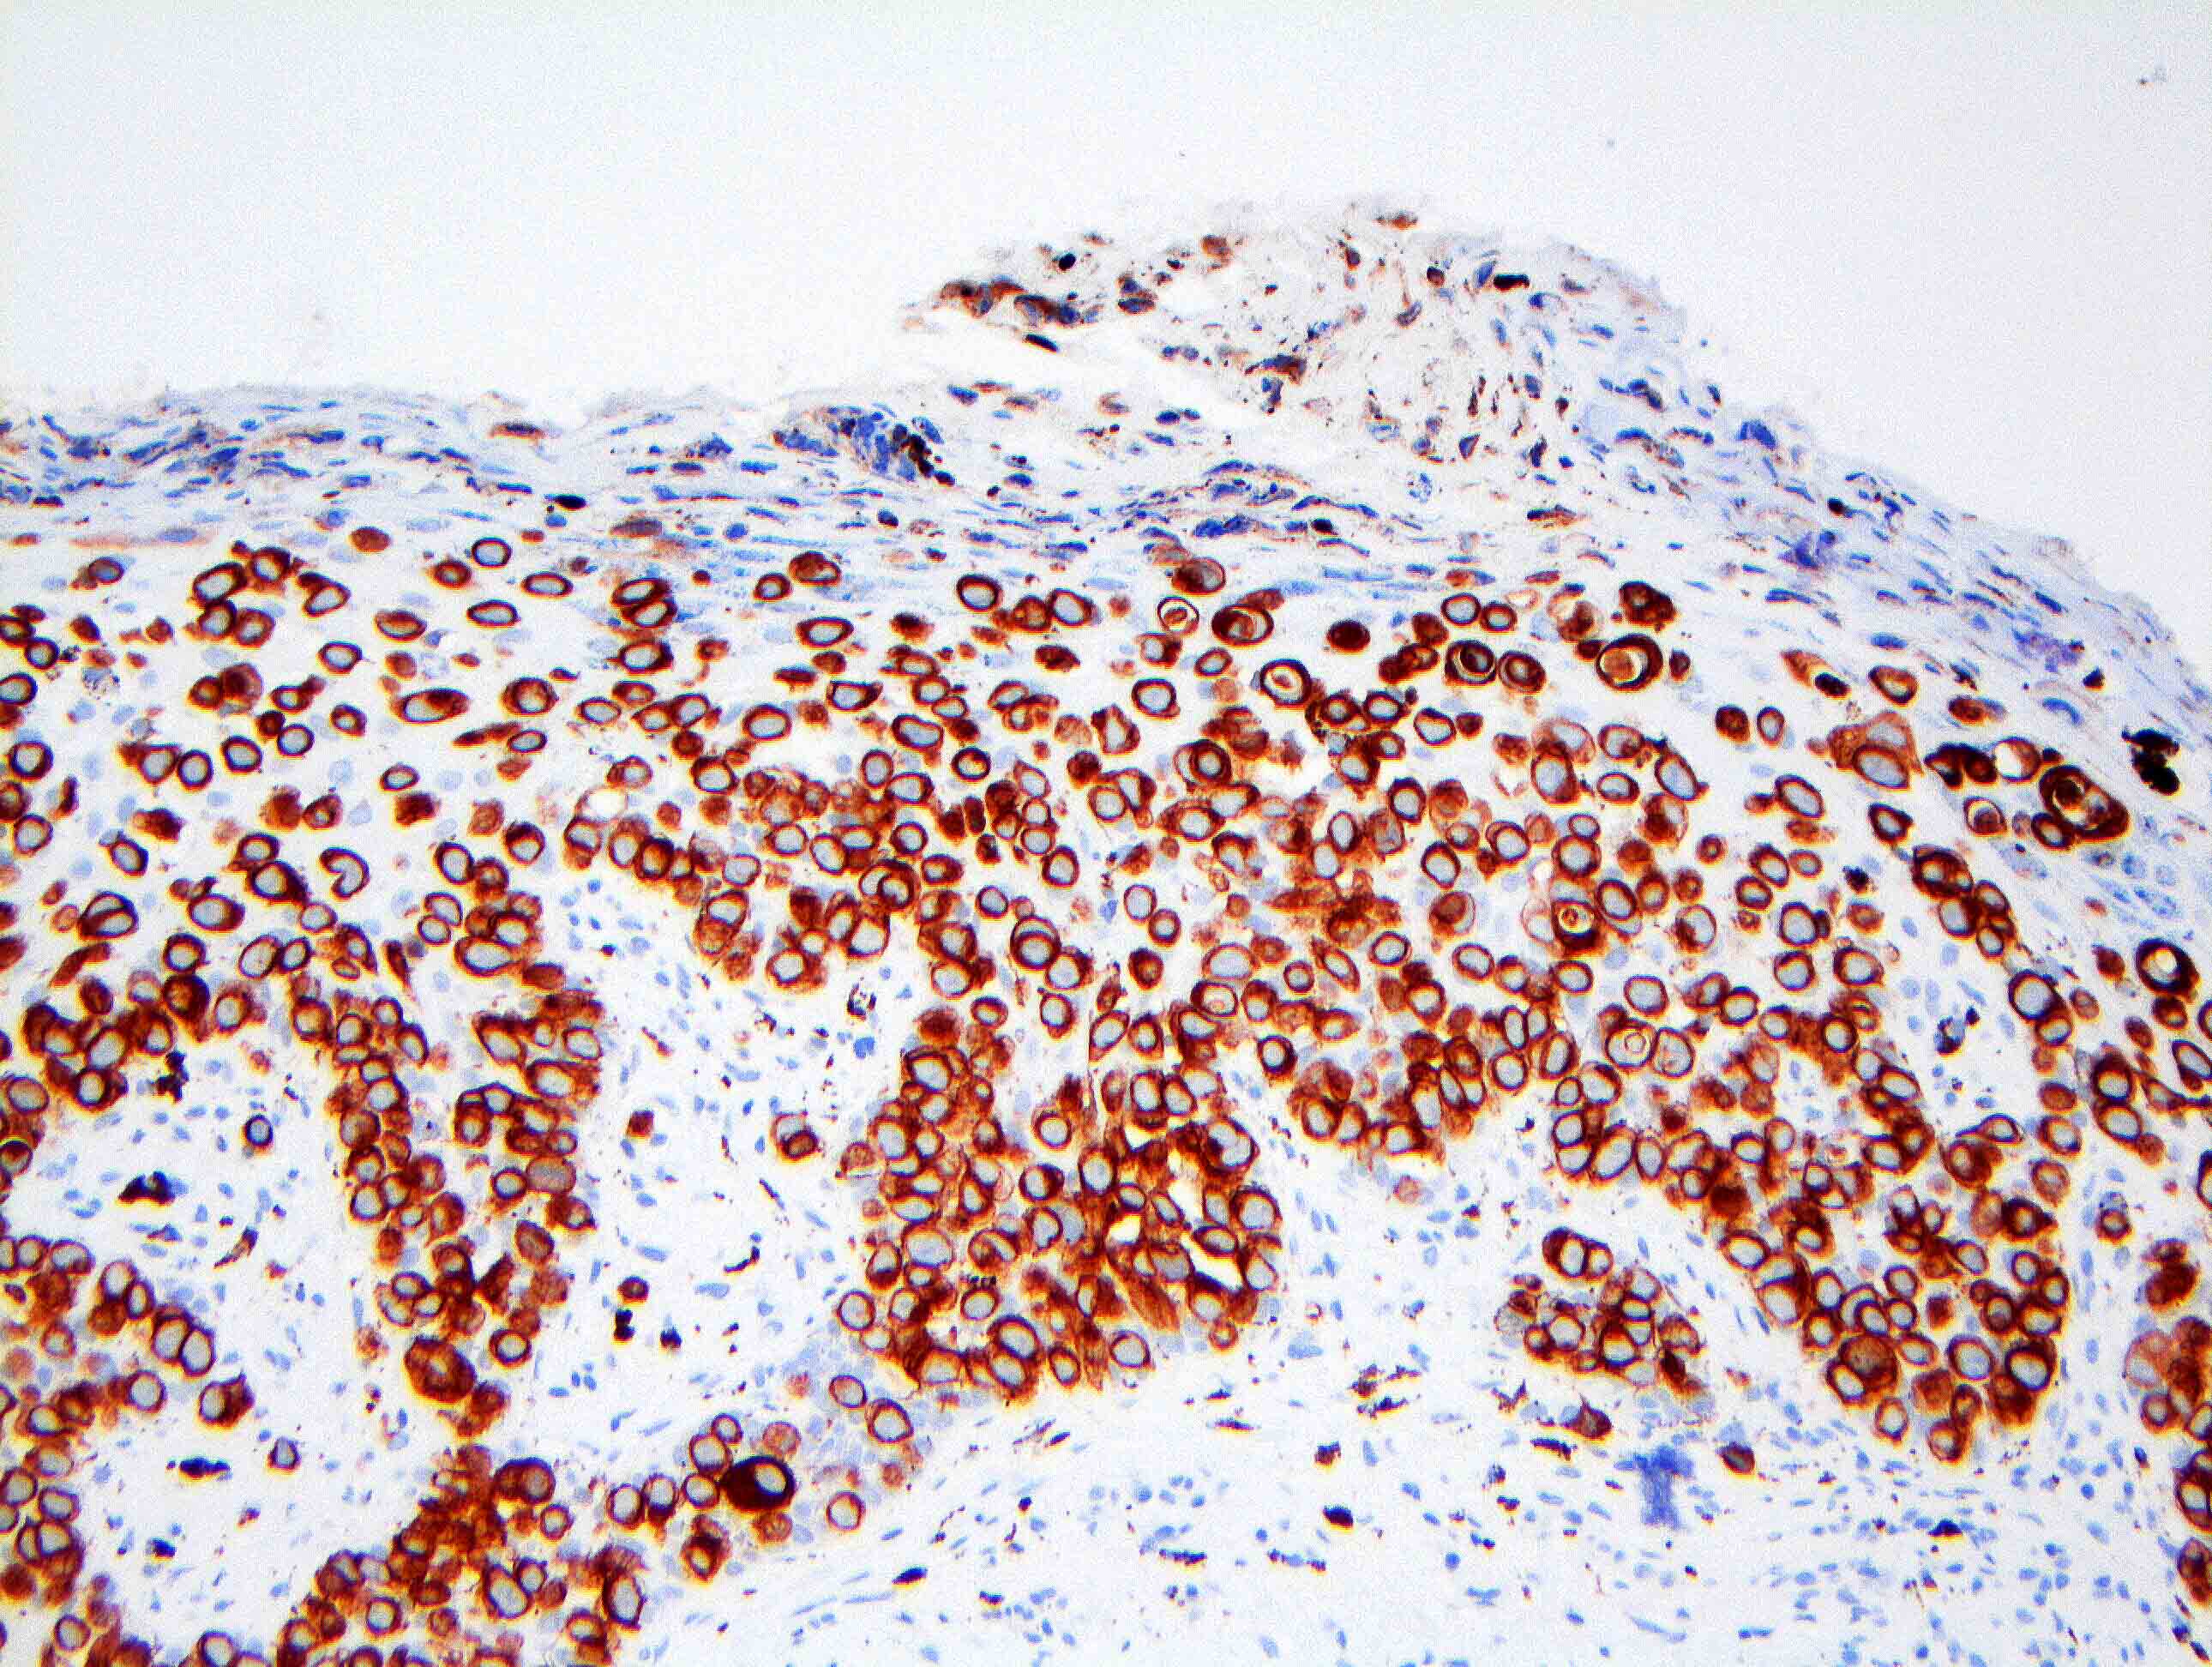

Microscopic (histologic) images

Contributed by Anna Biernacka, M.D., Ph.D. and Mary Ann Gimenez Sanders, M.D, Ph.D.

Positive stains

- CK7 (> 90%)

- HER2 (80 - 100%)

- CAM5.2 (70 - 100%)

- ER (10 - 40%)

- PR (0 - 30%) (Breast Cancer Res Treat 2013;141:1)

- Comment: The tumor cells are positive for CK7 and HER2 (3+) by immunohistochemistry, supporting the above diagnosis of Paget disease. ER and PR show no staining of in situ nuclei.